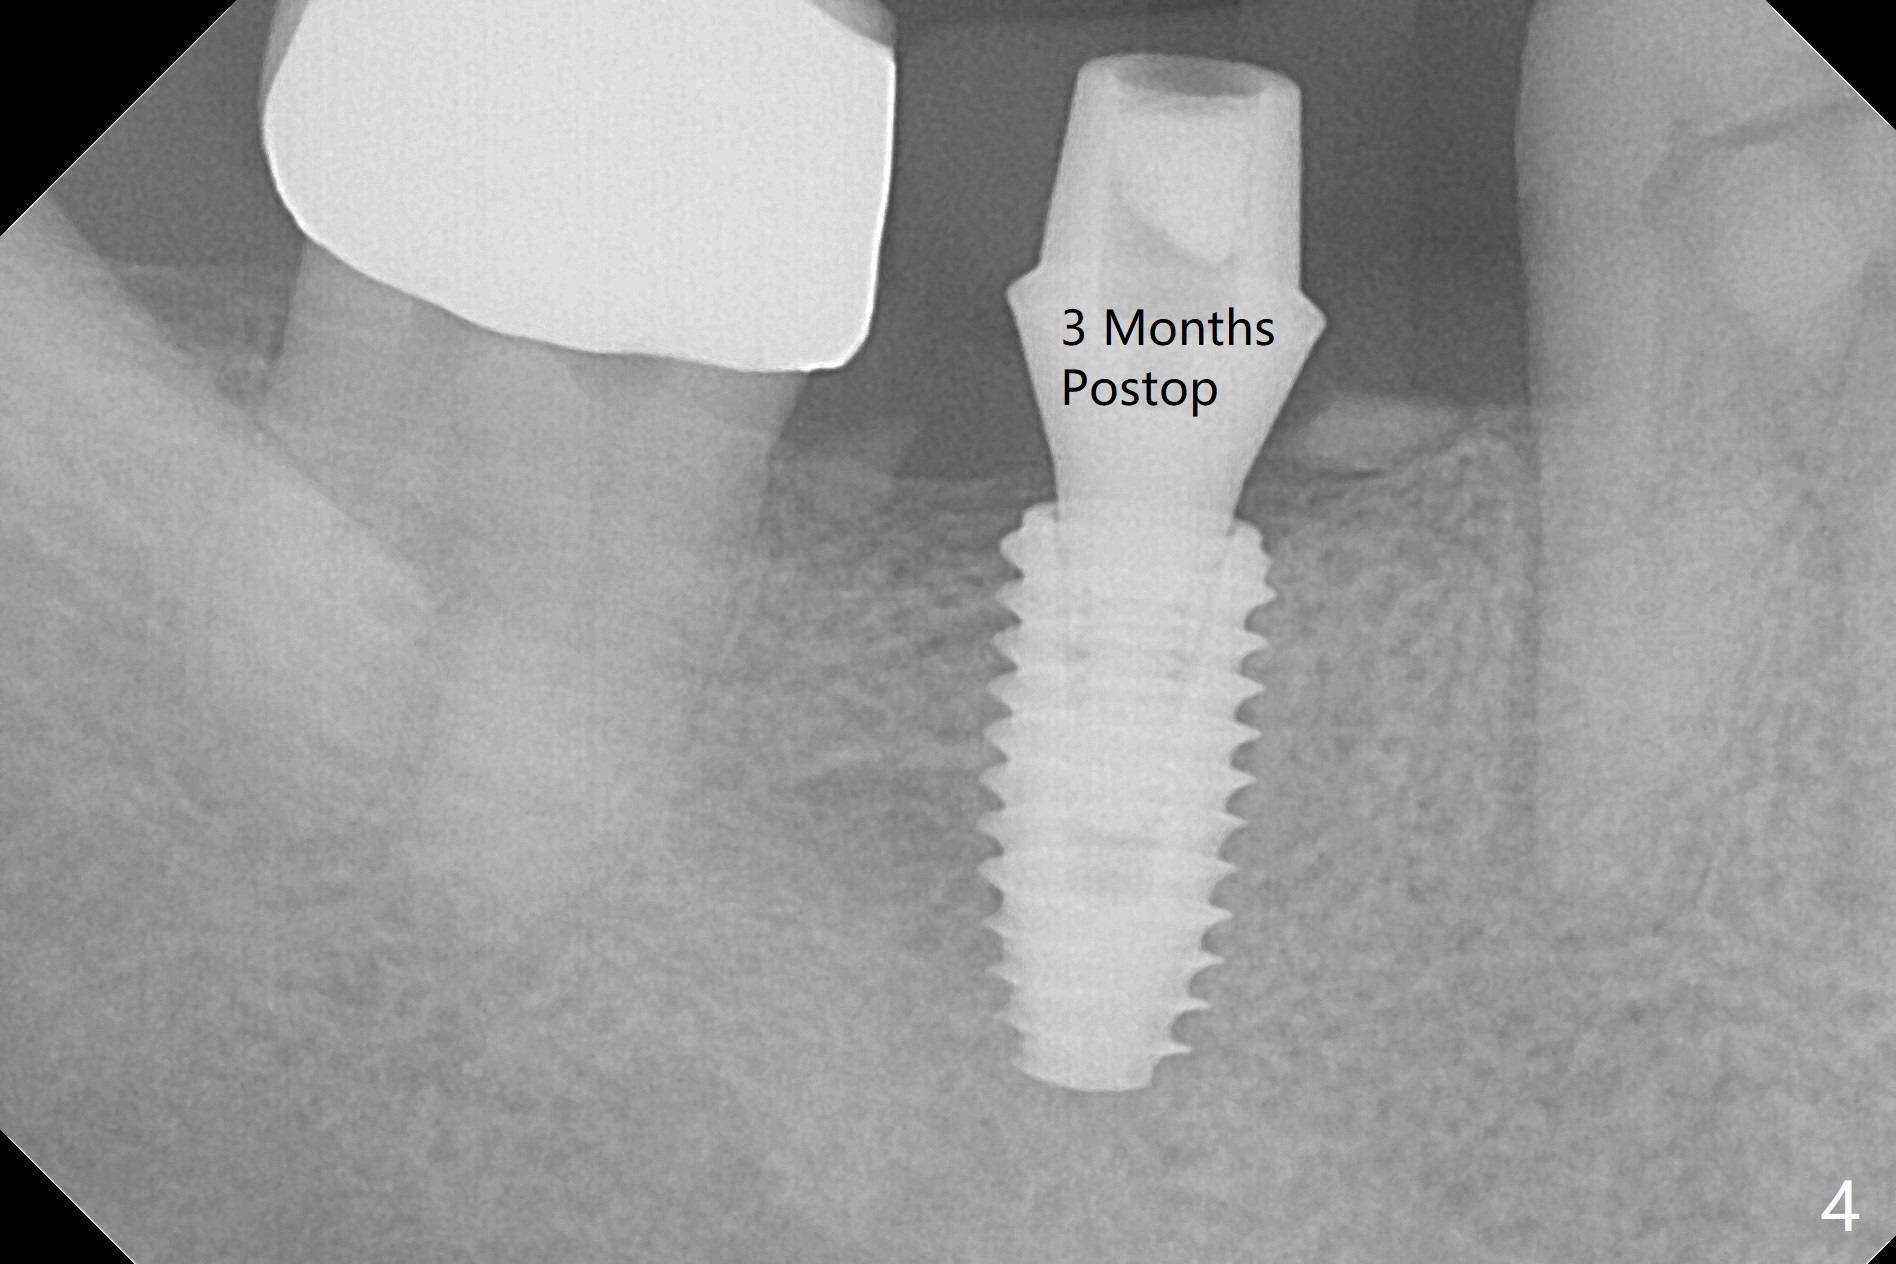

The edentulous ridge at #31 is anesthetized with one carpule of Lidocaine in an infiltration manner for guided surgery (Fig.1,2). In comparison, two or 3 carpules of Lidocaine are required for anesthesia for delayed implant placement without guide. It suggests that guided surgery is associated with less pain. Besides, the implant placed with guide has good trajectory and depth in a timely manner (Fig.3). Since the patient is a heavy bruxer with dislodgement of #30 provisional and #19 abutment screw loosening, a 5.7x4(3) mm cementation abutment is placed immediately so that a splinted provisional is fabricated for #30 and 31 for better retention. However, the gingiva around the implant at #31 is unhealthy 3 months postop (Fig.4). After impression, the provisional at #31 is sectioned without recementation for better oral hygiene. The distal gingival embrasure is large, associated with food impaction (Fig.5). Two years post cementation, the proximal contacts are trimmed (Fig.6 *) for pick up impression for crown repair. The implant and abutment contact is clearly shown with change in X-ray projection (Fig.7). When the new crown with flattened proximal contacts is being seated, it is tight mainly distal. After distal proximal contact adjustment, the crown is recemented without taking out crown/abutment for residual cement removal, because they may be unable to be completely seated because of the flattened larger proximal contacts (hand torque before impression).